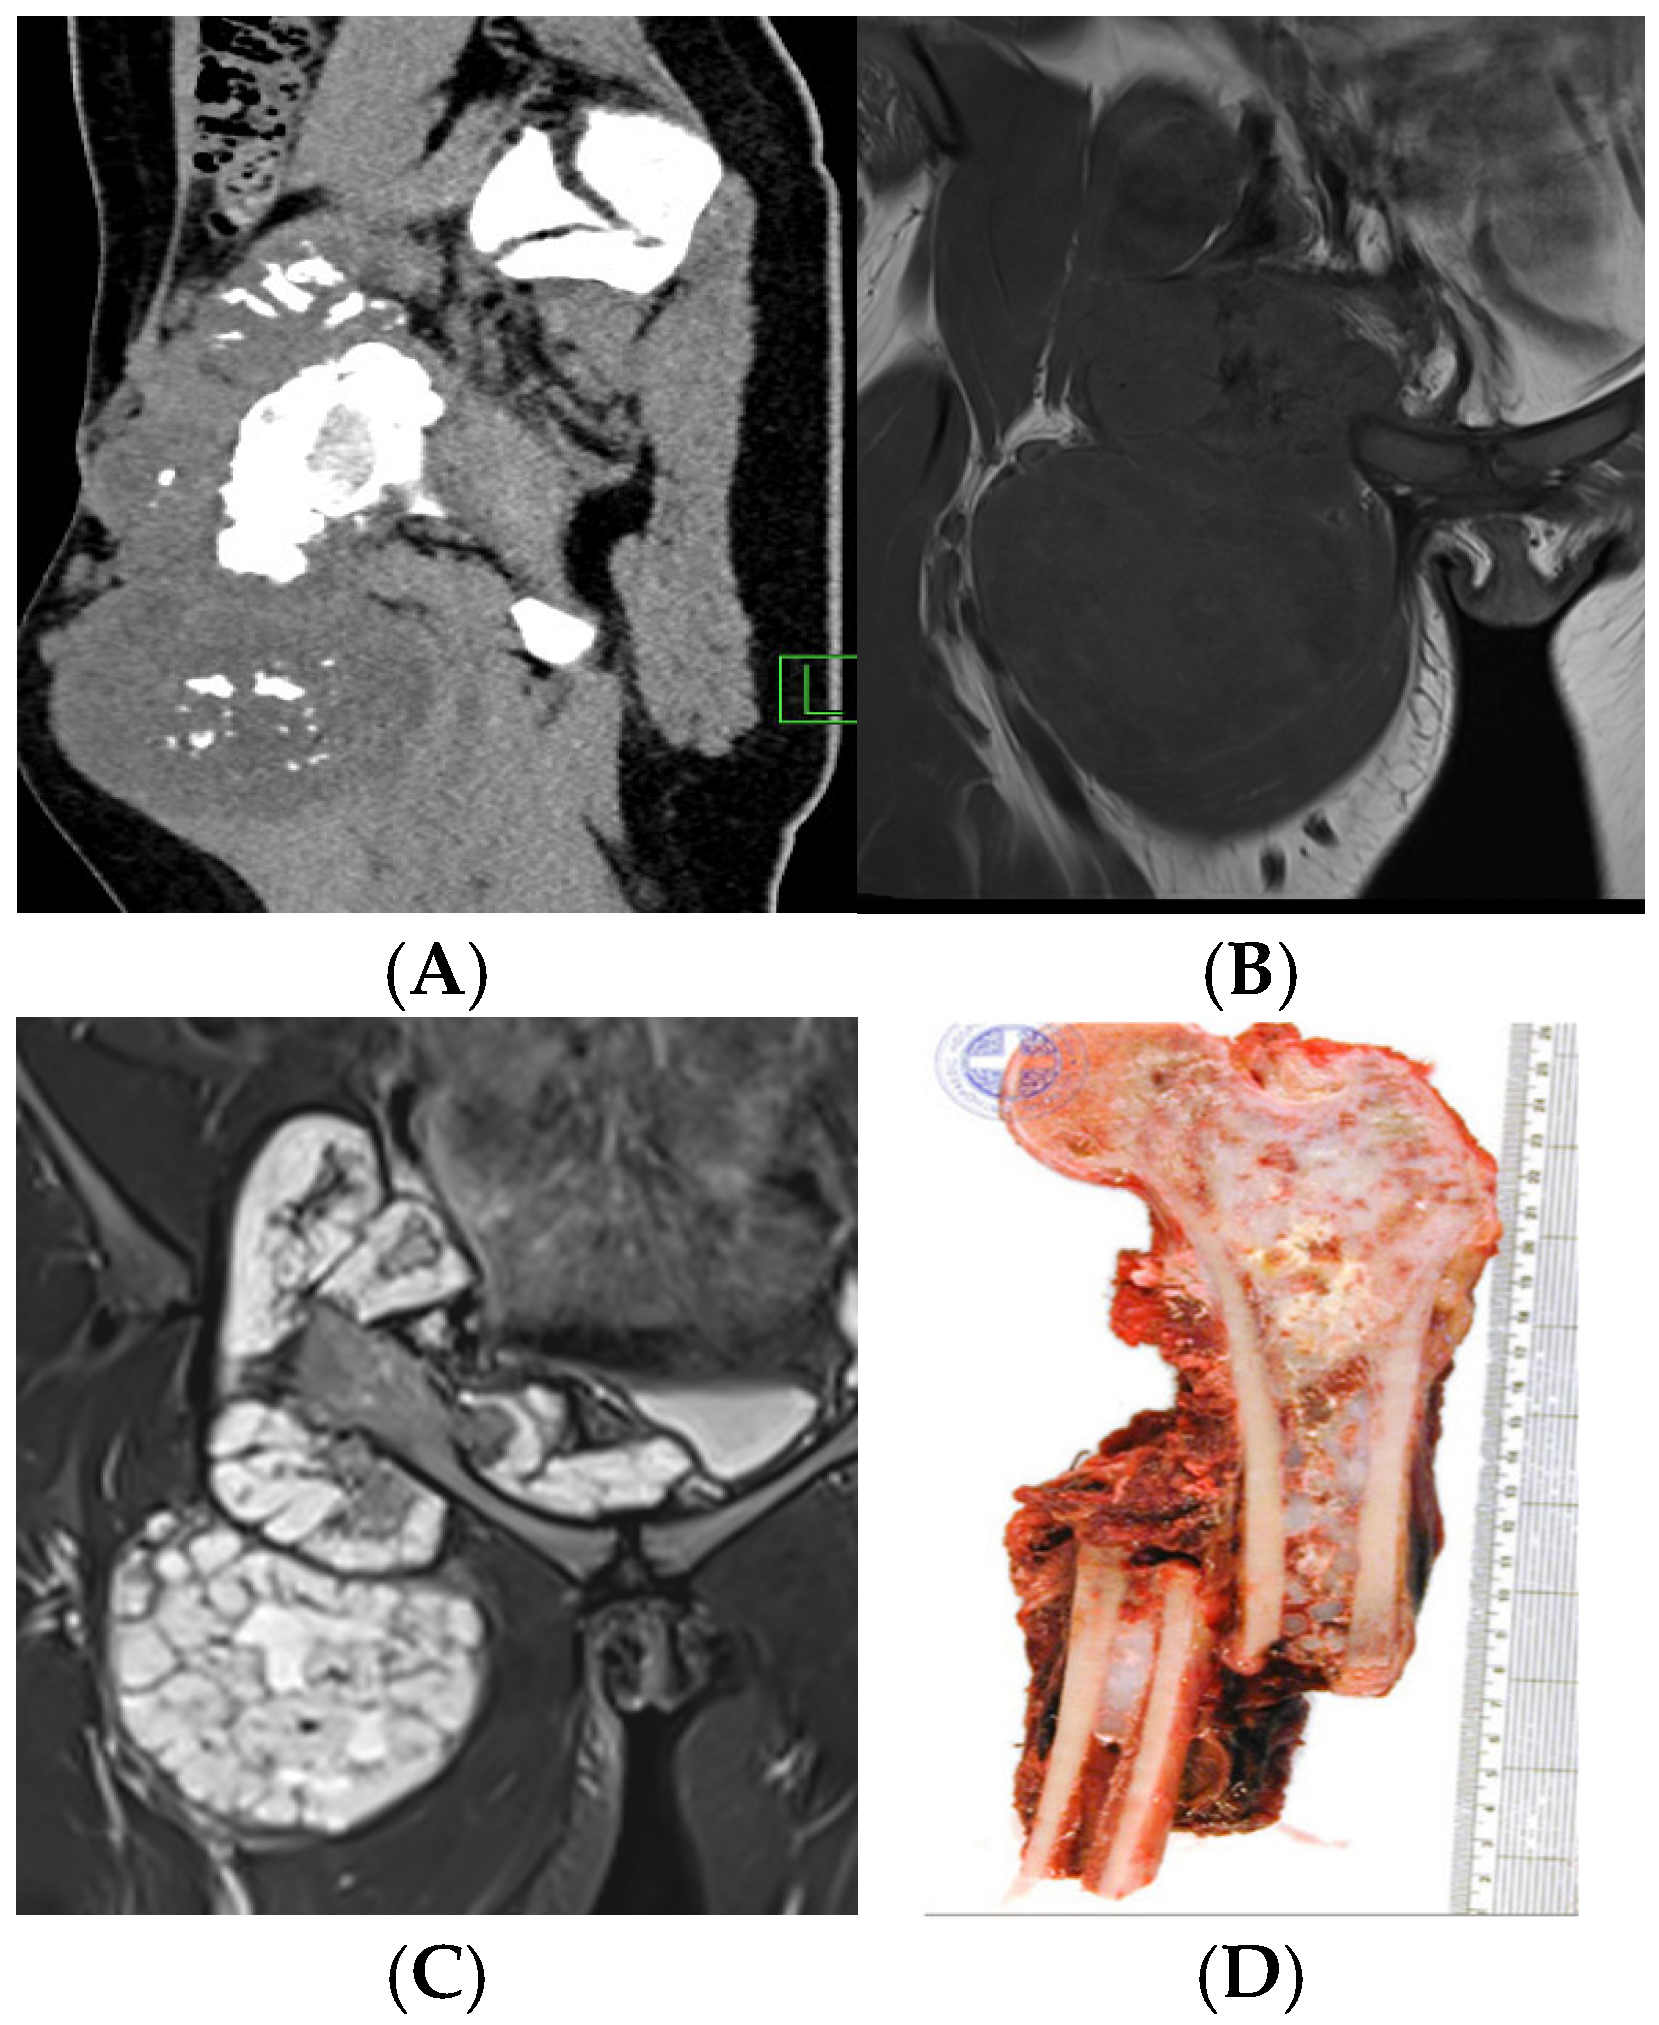

6.2. Chondrosarcoma

- Davies, A.; Patel, A.; Azzopardi, C.; James, S.; Botchu, R. Birmingham atypical cartilaginous tumour imaging protocol (BACTIP) revisited. Clin. Radiol. 2025, 83, 106837. [Google Scholar] [CrossRef]

- Janzen, L.; Logan, P.M.; O’Connell, J.X.; Connell, D.G.; Munk, P.L. Intramedullary chondroid tumors of bone: Correlation of abnormal peritumoral marrow and soft-tissue MRI signal with tumor type. Skelet. Radiol. 1997, 26, 100–106. [Google Scholar] [CrossRef]

- Alhumaid, S.M.; Alharbi, A.; Aljubair, H. Magnetic Resonance Imaging Role in the Differentiation Between Atypical Cartilaginous Tumors and High-Grade Chondrosarcoma: An Updated Systematic Review. Cureus 2020, 12, e11237. [Google Scholar] [CrossRef] [PubMed]